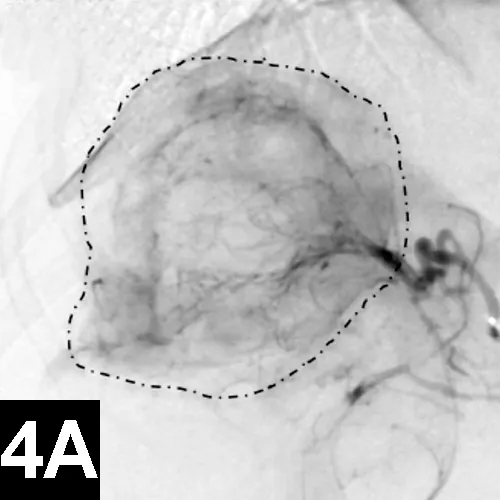

Chemoembolization involves selective delivery of intraarterial chemotherapy with subsequent particle embolization (Figure 4). Instead of administering systemic chemotherapy through a peripheral vein and exposing the patient to high systemic levels of these toxic drugs, local delivery into the arterial supply of the tumor has been shown to increase local drug concentrations, reduce systemic drug levels, reduce associated toxicities, and improve tumor response rates in humans with similar tumors.

Figure 4A: Lateral digital subtraction angiograms of a dog with a nonresectable massive right-sided hepatocellular carcinoma.

The dog’s head is to the left.

Prechemoembolization angiogram demonstrating a massive liver tumor (surrounded by hyphenated line).

The author has performed this procedure in cases of invasive sinus carcinomas and unresectable hepatocellular carcinomas in dogs with encouraging results.13

When chemoembolization is performed in dogs, the author has documented as low as 1/20th the peak concentration of circulating chemotherapeutic agent found systemically as well as systemic chemotherapy exposure, which in turn theoretically reduces the toxic systemic side effects and subsequently results in improved tumor response rates when compared with intravenous administration.